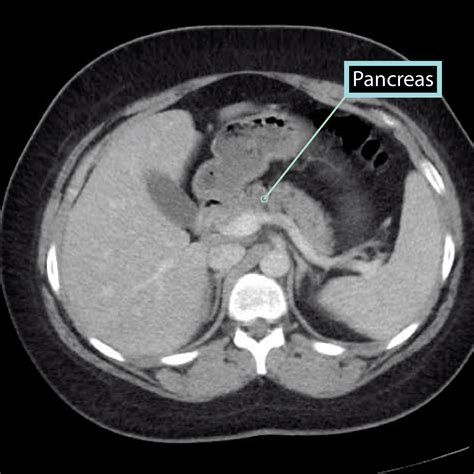

Pancreas Anatomy

Understanding the pancreas on CT scans is crucial for diagnosing and managing various pancreatic conditions. Computed Tomography (CT) scans provide detailed images of the pancreas, aiding in the detection of diseases such as pancreatitis, pancreatic cancer, and cysts. This blog post will delve into the importance of CT scans in pancreatic imaging, the preparation required for the procedure, and the interpretation of results.

CT scans are a cornerstone in the diagnostic process for pancreatic diseases. They offer high-resolution images that can reveal abnormalities in the pancreas, such as inflammation, tumors, or cysts. The detailed visualization provided by CT scans helps healthcare professionals make accurate diagnoses and develop effective treatment plans.

One of the primary advantages of CT scans is their ability to detect even small lesions in the pancreas. This is particularly important for early-stage pancreatic cancer, where timely intervention can significantly improve patient outcomes. Additionally, CT scans can assess the extent of disease spread, guiding surgical planning and other therapeutic interventions.